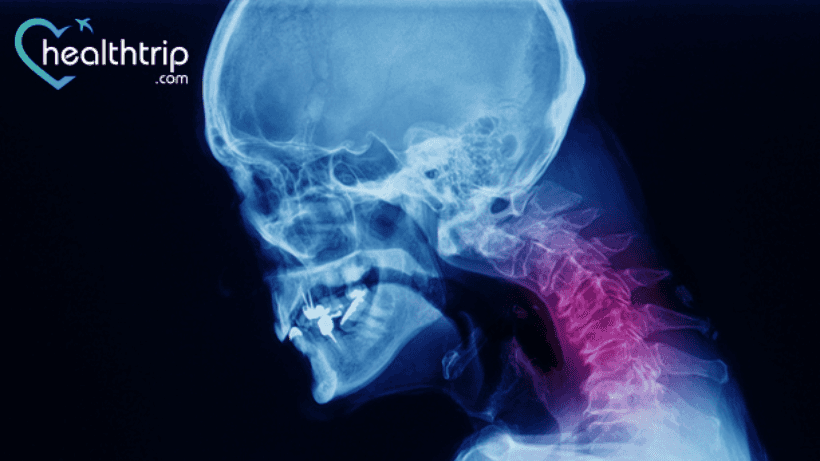

Every other surgery or procedure carries several risks and complications. But, even if the risk is low for some surgeries, you should not overlook the minute chances of developing serious complications. Here we’ve discussed the complications of anterior cervical discectomy and fusion surgery. Keep reading to learn the same.

Anterior cervical discectomy and fusion are usually recommended for patients who have cervical spondylosis or disc herniation with myelopathy/radiculopathy that is

unresponsive to conservative therapy. Additionally, it may be indicated in certain malignant, traumatic, or infectious processes of the cervical vertebrae that cause instability.

How is ACDF surgery done?

The procedure is performed through an anterolateral neck incision, with the surgical approach passing medially between the aerodigestive tract (trachea, esophagus, pharyngeal muscles) and laterally between the carotid neurovascular bundle (carotid artery, internal jugular vein, vagus nerve).

The intervertebral disc and the fibrocartilage covering the adjacent vertebral endplates are then removed (to allow for eventual osseous fusion). Reaching back to the posterior longitudinal ligament, removing osteophytes and disc protrusions as well as extending laterally to decompress the neural exit foramina, is possible.